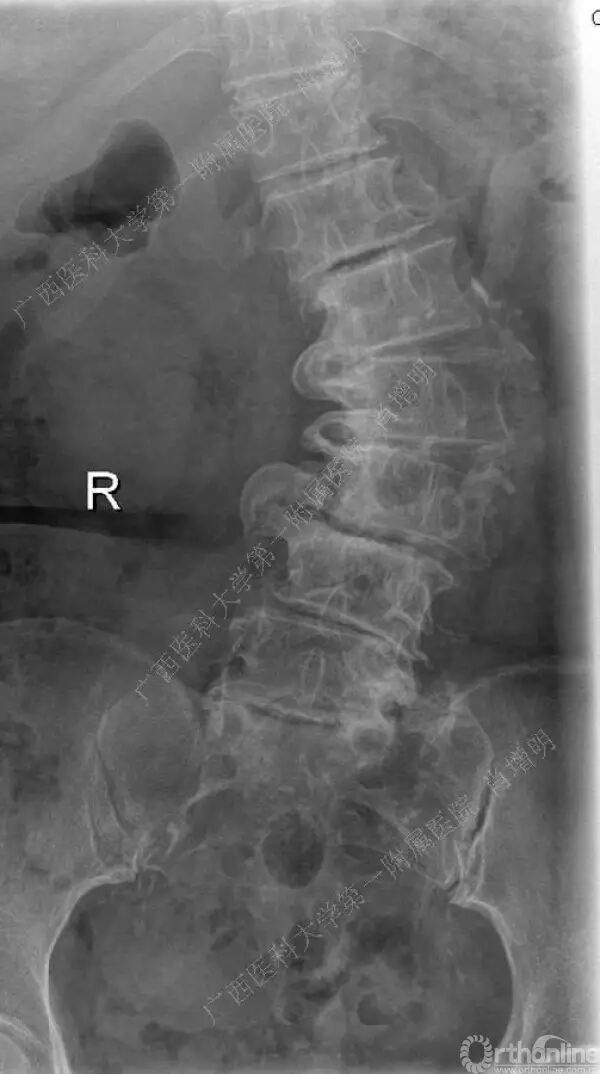

退变性脊柱侧凸是由于椎间盘退变后继发小关节退变,椎管和神经根管容积变化以及脊柱失稳,畸形等病理改变,以疼痛和神经压迫症状为主要表现的常见疾病。

退变性脊柱侧凸多发于50岁以上的中老年群体,是现代常见的老年疾病。多年来,针对该病的临床研究一直没有停步,广西医科大学第一附属医院肖增明教授细致地介绍了该病的诊疗进展。